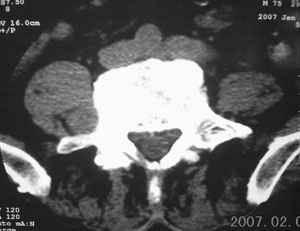

男,75岁,腰周疼5-6年。别无症状。

右侧椎旁、侧隐窝软组织肿块,呈不规则双极征改变,椎体后外缘骨质弧形压迹,椎间孔扩大;考虑神经源性肿瘤,神经鞘瘤可能性大,需与神经纤维瘤相鉴别。

起源于右侧神经根的神经鞘瘤。mr有用。

病变侧椎间孔扩大,椎体缘受压吸收,考虑神经源性肿瘤(神经鞘瘤可能)。